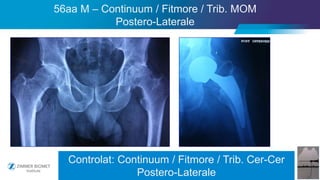

56aa M – Continuum / Fitmore / Trib. MOM

Postero-Laterale

Controlat: Continuum / Fitmore / Trib. Cer-Cer